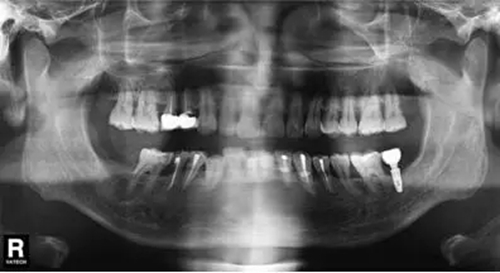

圖6 拔除47前曲面體層片

臨床檢查47面見大面積充填物,冠近遠(yuǎn)中折裂,叩痛(+),松動度(-),牙齦(-)。曲面體層片示46髓腔內(nèi)及根管見高密度影像,根尖未見明顯陰影(圖6)。